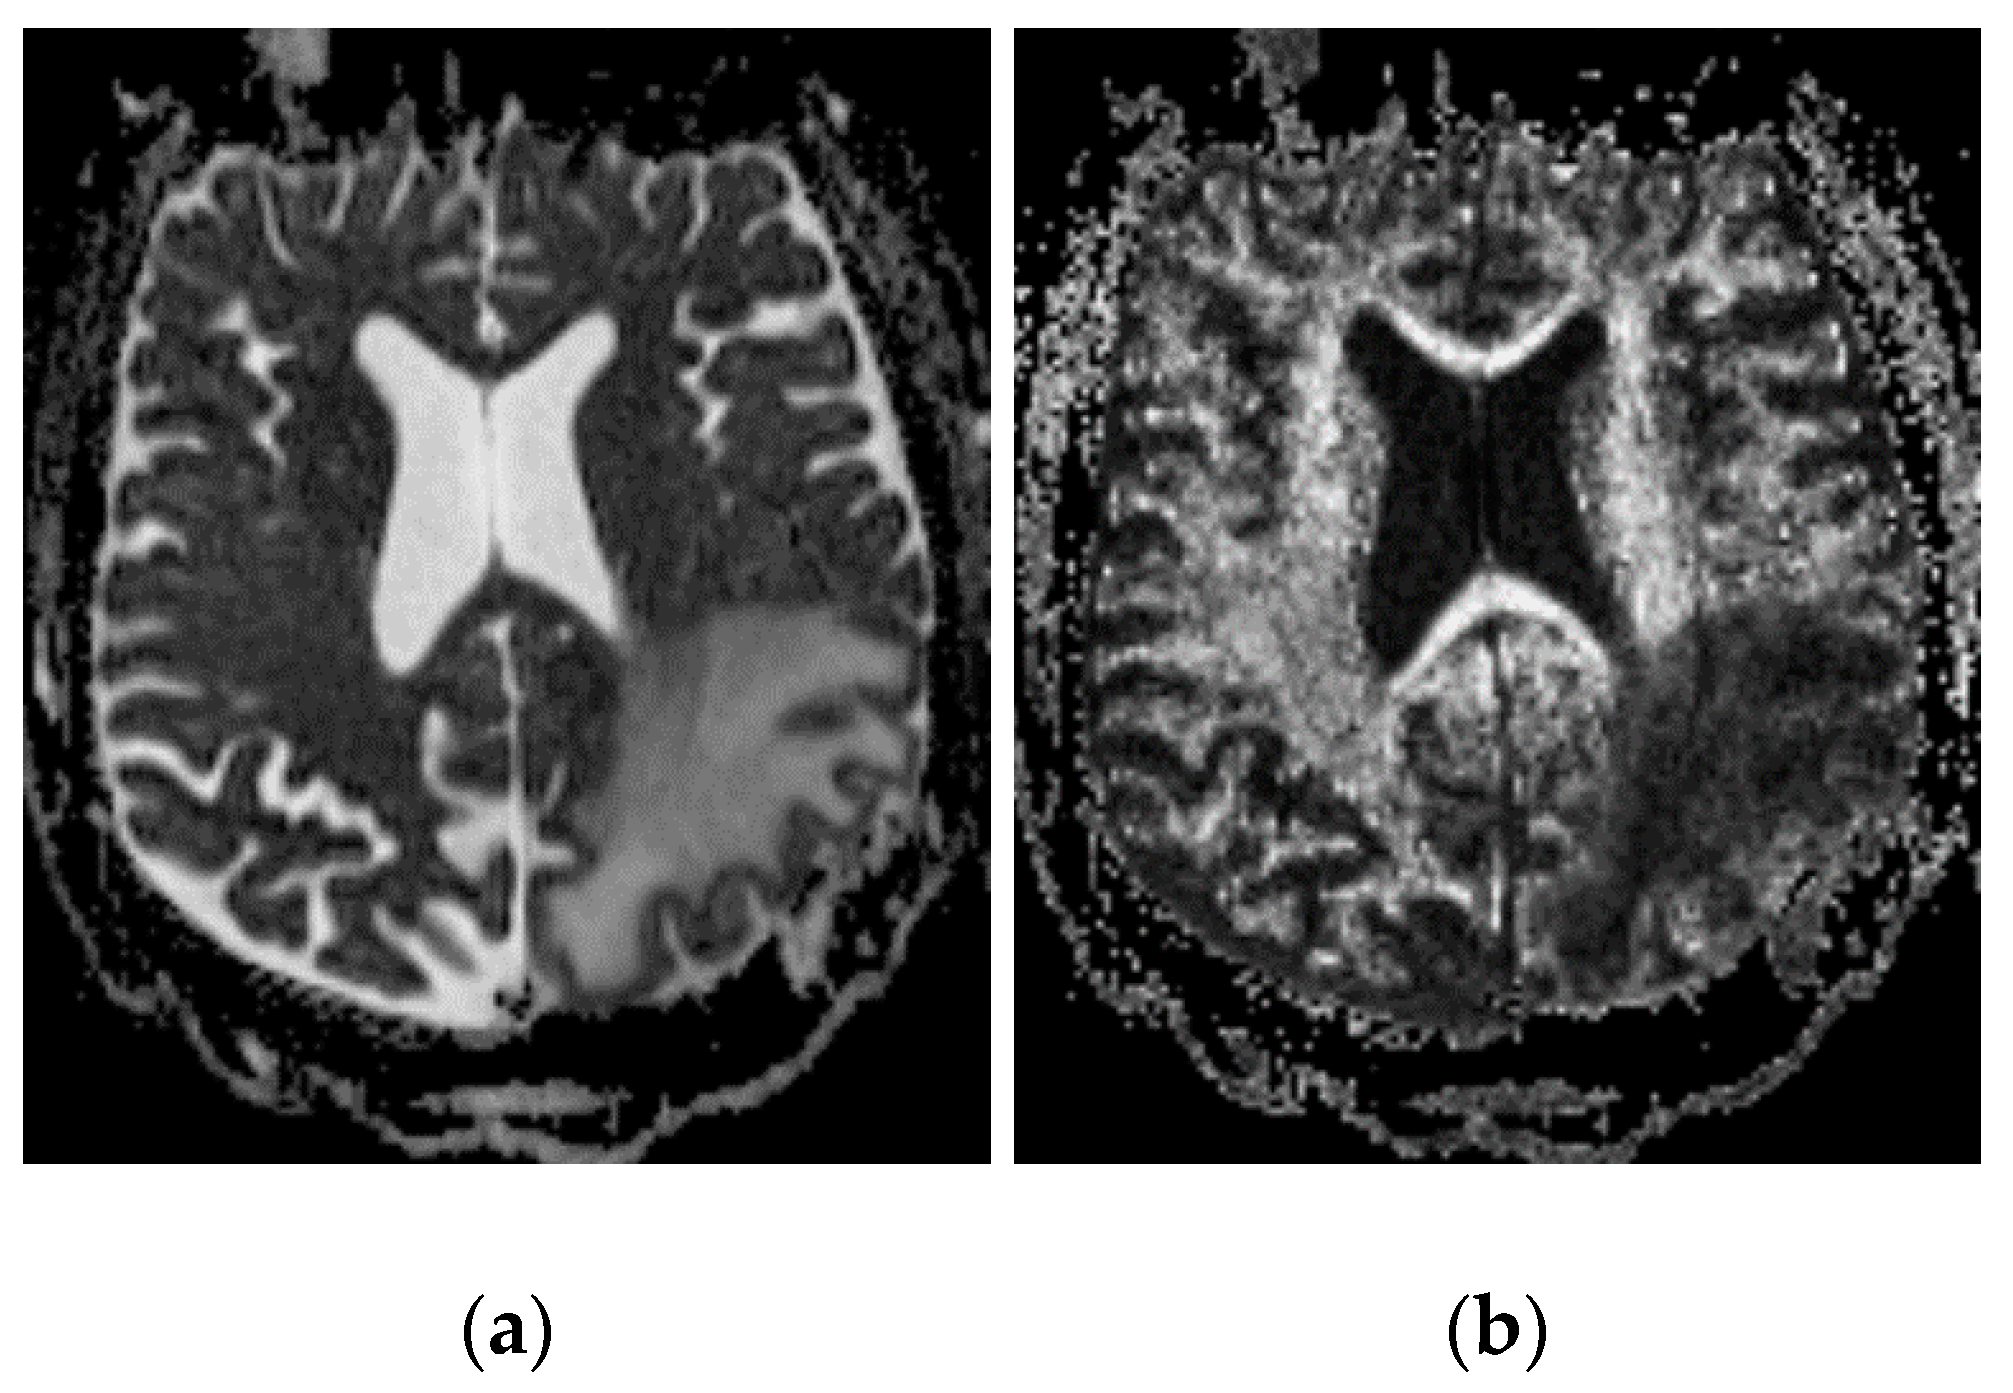

2.2.2. Imaging Protocols

2.2.3. Concentration Measurement

2.2.4. Distribution Volume Measurement